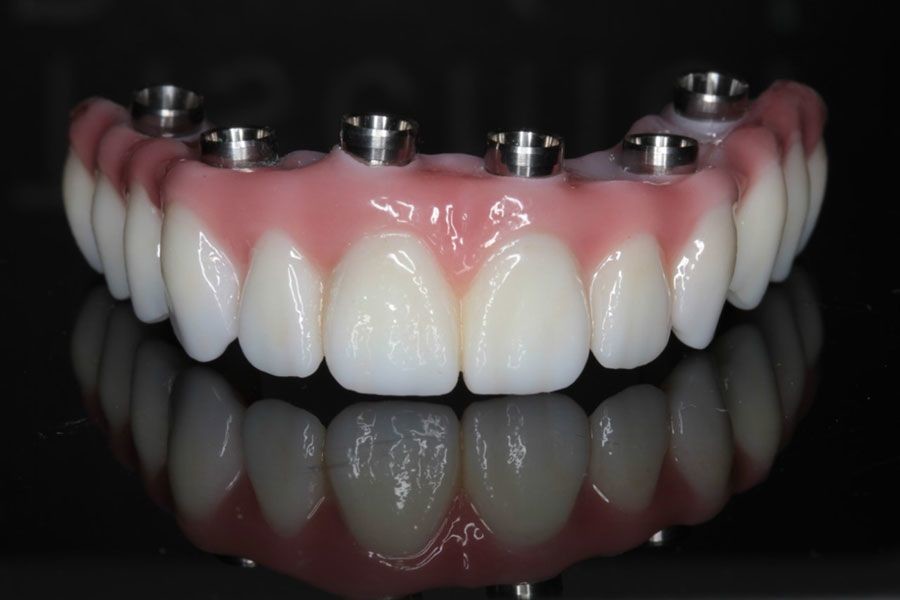

What Happens During a Full Mouth Reconstruction?

Has your general dentist told you that you need a full mouth reconstruction to restore your teeth and smile? This is an important procedure for your health and the aesthetics of your teeth. You will likely go into your procedure with some questions and concerns. It is helpful to understand what will take place at the dentist’s office and what the results will look like. You can rest at ease knowing that there are many benefits to repairing damaged teeth and replacing missing ones.

After the consultation, the dentist will do some preparatory work. This will include taking X-rays and making impressions of the mouth. This information will be important in making devices, such as crowns, veneers, bridges, implants, or dentures. Before a dentist can start treating the patient’s condition, tooth extraction may be necessary.

Some full mouth reconstruction procedures require work on the tooth before the dentist places the device. For crowns, the dentist must first reshape the tooth by shaving part of it off. This helps ensure that the cap will fit. For veneers, the dentist first removes a bit of enamel and roughens the tooth so the veneer will bond to it. If the patient is getting bridges, the dentist will first place crowns over the teeth adjacent to the gap in the mouth.